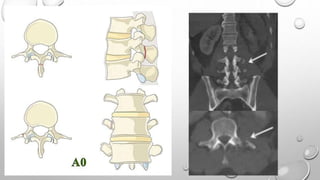

Tipo A

Describen daño del cuerpo vertebral sin

compromiso de la banda de tensión.

A0: Fractura no estructural, menor

A1: Compresión en cuña

A2: Separación, División

A3: Estallido incompleto

A4: Estallido Completo